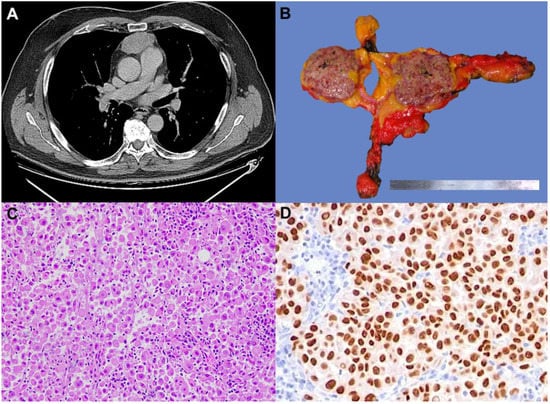

The second patient was a 62-year-old man with a history of skin melanoma of the cervical region which had been surgically resected in 2016. The pathological stage was pT2a, and the tumor harbored the BRAF V600E mutation. One year later a distant relapse to the right foot occurred and was treated with radiotherapy and immunotherapy. After almost five years of controlled disease, a total body CT scan revealed a retrosternal well-defined mediastinal mass of 27 × 30 × 44 mm (Figure 2A), hypermetabolic (SUV = 11.8) at 18-FDG-PET/CT scan. The case was discussed in a multidisciplinary setting; considering the unique localization without metastases in other sites and the radiological features of the mass, a surgical approach was proposed because a primitive neoplasm of the thymus was suspected. A standard robotic-assisted thymectomy was performed. Gross examination showed a brownish nodular mass (Figure 2B). At histology, the tumor was composed of irregularly shaped and eosinophilic neoplastic cells, strongly and diffusely immunoreactive for melanocytic markers (SOX10, Melan A, S100, HMB45). Based on histological and immunohistochemical examination, the diagnosis of intrathymic metastasis of melanoma was made (Figure 2C,D). A large panel of NGS was carried out to identify rare mutations or co-mutations that may have occurred. The tumor showed BRAF mutation (V600E) as the primitive melanoma. No additional mutation has been reported. After surgery, the patient started adjuvant treatment with Nivolumab at a dosage of 480 mg every 4 weeks. Currently, the patient has completed eight cycles of treatment with no reported toxicities. One year after surgery, the patient remains under follow-up and is in good health.

Figure 2. CT scan showing a well-defined retrosternal mediastinal mass (A). Gross specimen showing a nodular mass, which is brownish at the cut surface (B). The tumor was composed of large and atypical cells with abundant eosinophilic cytoplasm (C) (hematoxylin and eosin stain, original magnification ×100). Tumor cells showing nuclear positivity for SOX10 (D) (immunohistochemistry, original magnification ×200)).